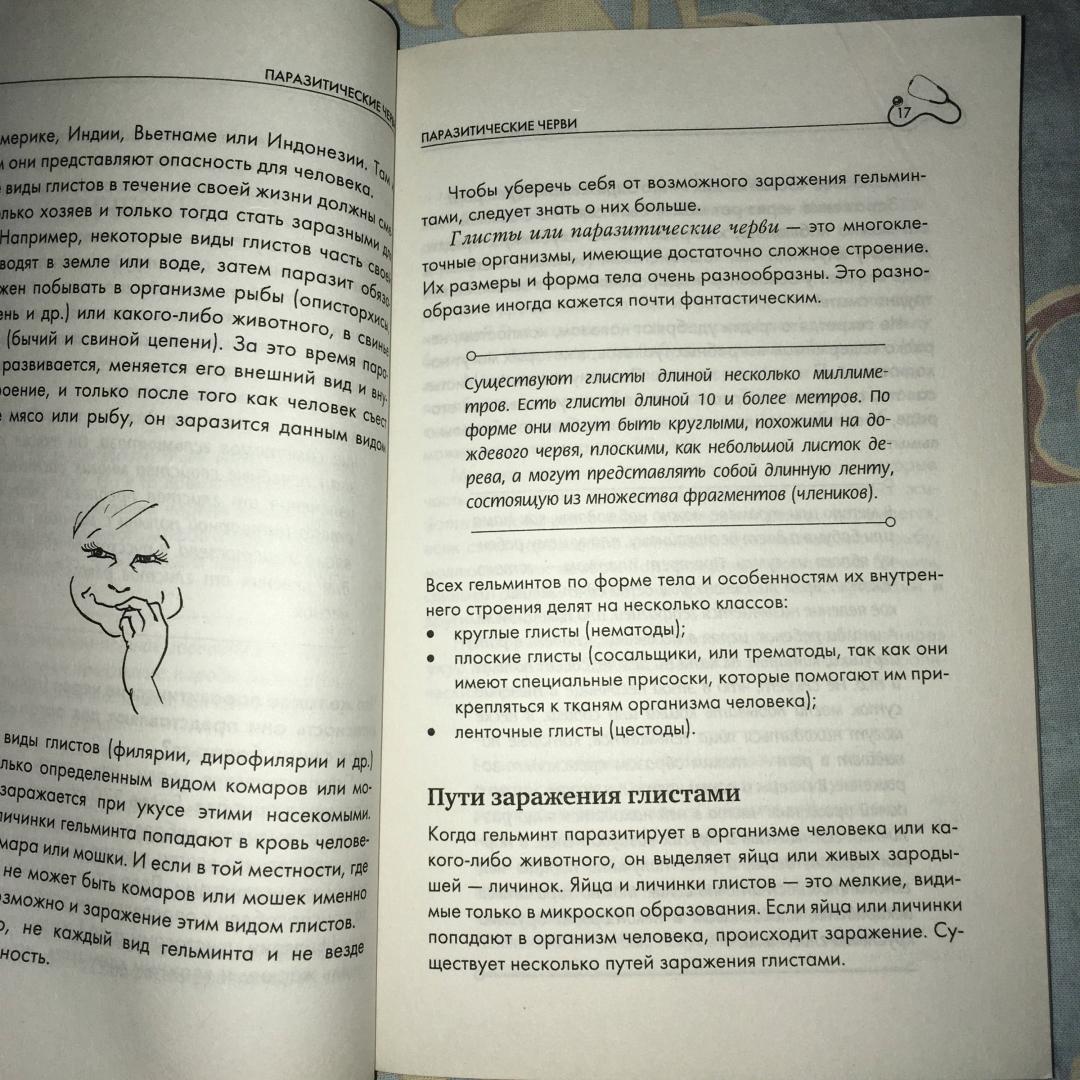

Фотографии нематод, цестод и трематод в природе

Раздел: Другие животные